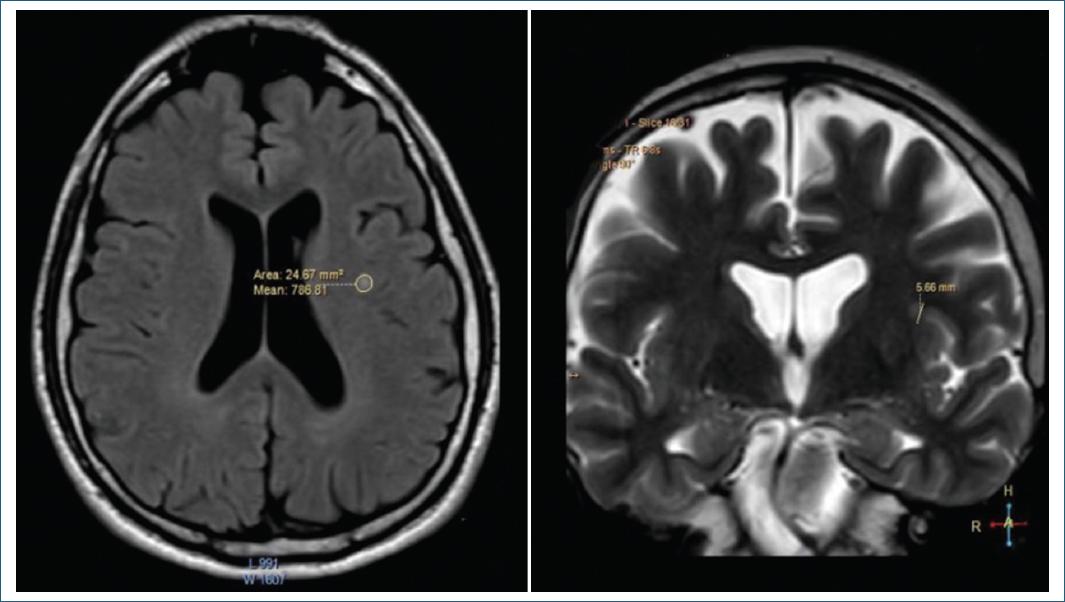

Se observó un infarto lacunar izquierdo aislado y datos de atrofia frontoparietal leve en la imagen por resonancia magnética (IRM) encefálica (Fig. 1).

Aunque el infarto lacunar fue uno de los principales hallazgos de nuestro caso, no había factores de riesgo cardiovascular que apoyaran dicho diagnóstico

No obstante, las alteraciones cognitivas del paciente sí son posibles en la EA, la DV y la DFT. En cualquier caso, los antecedentes familiares eran negativos para trastornos neurodegenerativos. Además, sus fallos de memoria son tanto verbales como visuoespaciales y no asociados a la memoria episódica anterógrada, lo cual es indicativo de la integridad de ambas áreas hipocampales (algo que también confirmaron las IRM). Es raro que la enfermedad de Alzheimer no afecte las áreas mencionadas9.

Las características de la lesión de nuestro paciente fueron un infarto lacunar derecho aislado y atrofia frontotemporal bilateral leve. Estos últimos hallazgos difieren de la atrofia temporal que suele observarse en pacientes con EA9.

Quizás la anosognosia pueda explicarse por las alteraciones frontoparietales del paciente, una patología que viene provocada por cambios tanto en el lóbulo parietal inferior derecho como en las áreas corticales implicadas en la red neuronal por defecto (centros de auto-monitorización)11.

No obstante, se requieren valoraciones más profundas mediante imágenes funcionales para los hallazgos de las IRM en este paciente, ya que en la literatura se han descrito cambios cerebrales parecidos secundarios al COVID persistente10.